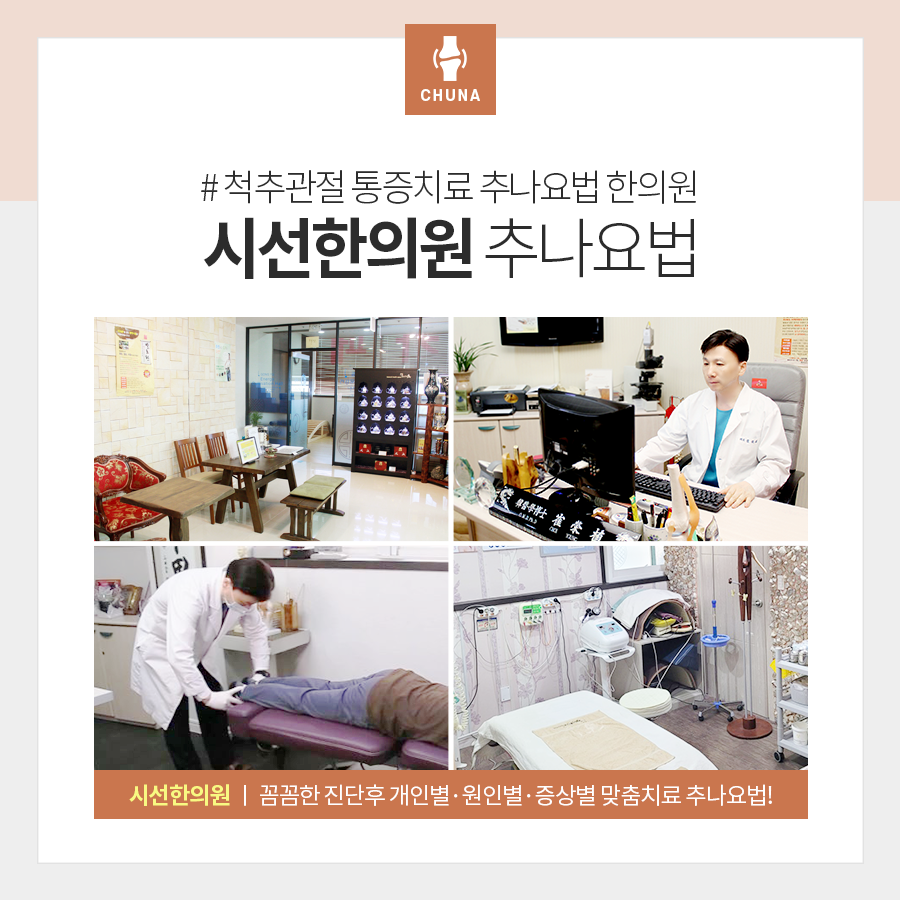

동래부나 한방병원에서는 개인의 현재 상태를 파악하기 위하여 어깨 관절을 비롯한 어깨 중심의 관절 검사를 실시합니다. 여기서 견관절이란 앞서 언급한 어깨를 360도 움직일 수 있는 넓은 가동 범위의 관절로, 가동 가능한 범위를 포함하여 전반적인 기능을 체크하고 손상 척도를 확인합니다.이 밖에도 갈비뼈나 사각근 등을 확인함으로써 증상의 심각성과 원인을 알아보고 사진검사와 보행자세 분석, 체성분, 어깨높이 등을 측정하여 신체 전반의 균형을 확인할 수 있습니다.

확인된 결과, 진행되는 치료의 방향에는 차이가 있지만 기본적으로는 통증의 경감과 함께 근골격의 기능적 이상이나 운동 범위의 회복에 집중합니다.

일상에 불편을 주는 주요 증상이 통증과 운동성의 제한인 만큼 동래한의원에서는 어깨측의 다양한 관절 중 움직임에 관여하는 견흉관절과 흉쇄관절측을 중심으로 관절 가동 및 신연의 추명을 시행합니다. 이때 견흉관절은 견갑골 부근, 흉쇄관절은 쇄골 부근에 위치하고 있습니다.

증상 자체에는 유사점이 있다고 하더라도 원인에는 차이가 존재할 뿐만 아니라 추수학적 지식을 수반해야 하는 만큼 치료를 하려면 개인의 상황에 대한 면밀한 분석이 우선되어야 한다는 점을 다시 한번 안내 드립니다.